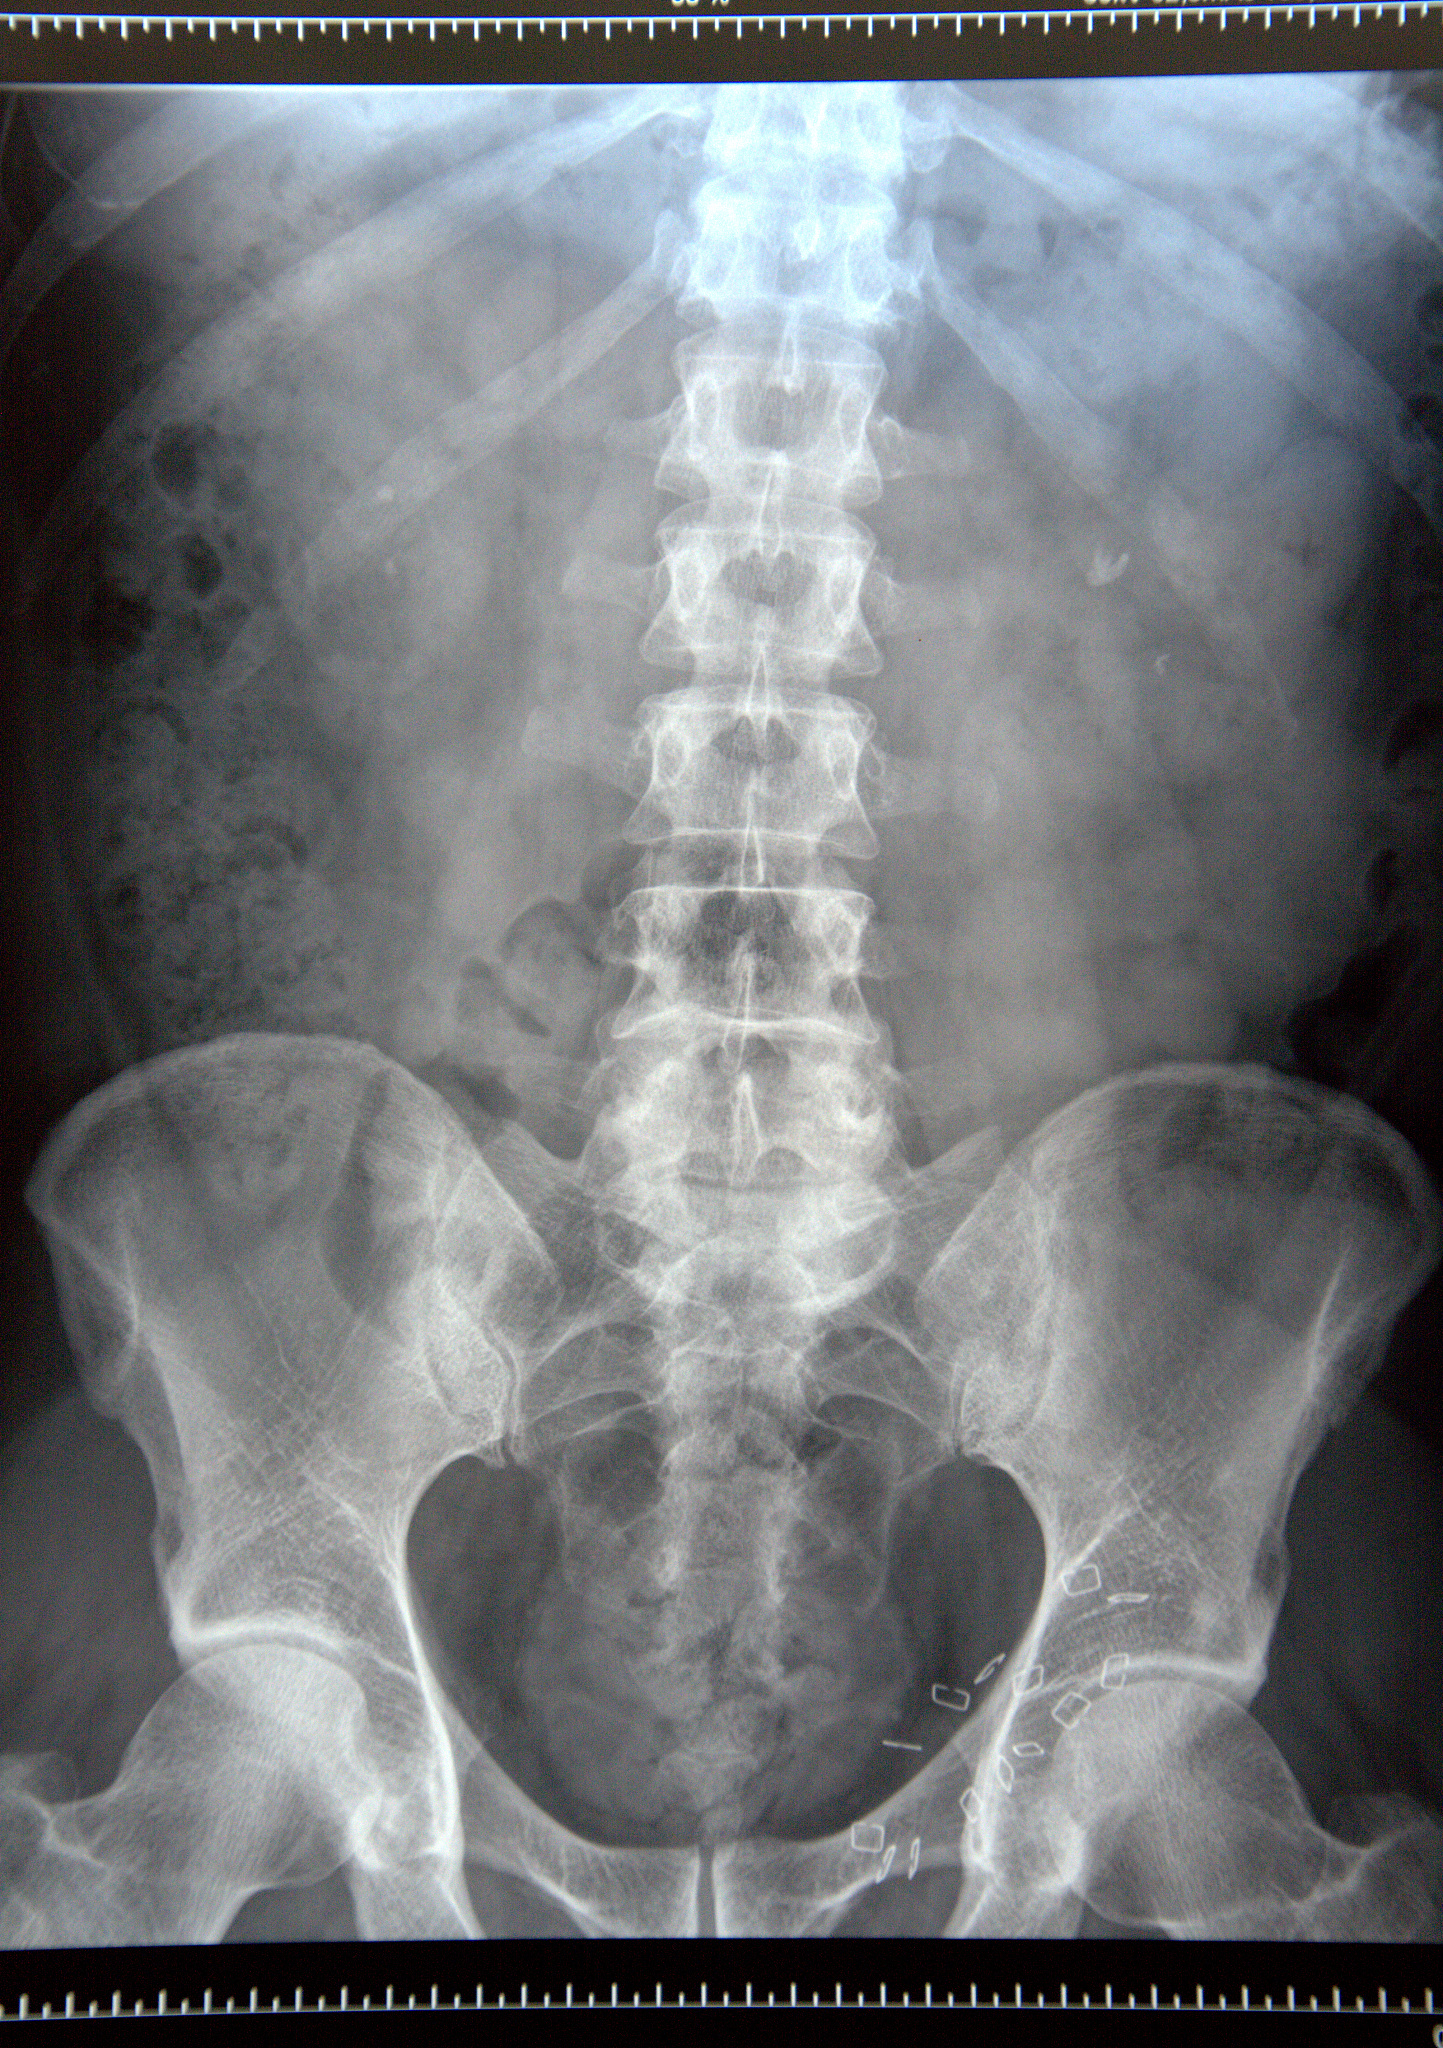

"泌尿系结石科普:成因、症状、治疗和预防"\n\n泌尿系结石是一种常见的疾病,它是由于身体内某些物质在尿液中过度浓缩而形成的固体结晶体。结石可出现在肾脏、尿道、膀胱等部位,给患者带来疼痛和不适。了解结石的成因、症状、治疗方式及预防措施,将有助于我们更好地预防和处理这一问题。\n\n结石的成因多种多样,其中最常见的是尿液中的某些物质浓度过高,超过了尿液所能溶解的范围,形成结晶体。这些物质包括钙、尿酸、草酸盐等。其他因素如饮食习惯、遗传因素、药物使用和某些疾病也可能增加结石的风险。\n\n结石的症状多种多样,轻微的结石可能没有任何症状,而大多数患者会经历剧烈的腰部或腹部疼痛,伴随着尿血、尿频、尿急等症状。有时结石也会引起尿路感染,患者可能出现发热、恶心、呕吐等症状。\n\n对于结石的治疗,选择的方法取决于结石的位置、大小和类型。小尺寸的结石可能会通过饮水和药物来促进结石的排出。大尺寸的结石可能需要进行外科手术或者利用体外冲击波碎石术等无创治疗方式来摧毁结石。对于复发性结石患者,可能需要进一步的检查和治疗,以了解和纠正潜在的原因。\n\n预防是最重要的措施之一。饮食调节是预防结石的关键,包括增加水分摄入、减少摄入高盐、高蛋白质和高草酸盐的食物等。此外,保持适当的体重、规律的运动、避免长时间憋尿以及遵医嘱使用药物也是预防结石的重要措施。\n\n在治疗结石方面,我们的医院拥有先进的设备和专业的医护团队,致力于为患者提供全面的诊断和治疗服务。我们拥有一流的泌尿系结石科,采用最新的技术和方法,能够准确诊断和有效治疗各种类型的结石病例。我们的医护团队经验丰富,能够为患者提供个性化的治疗方案,并且在治疗过程中注重患者的舒适和安全。\n\n总之,了解泌尿系结石的成因、症状、治疗方式及预防措施对我们预防和处理结石问题至关重要。通过饮食调节、保持适当的体重和规律的运动,我们可以减少结石的风险。同时,选择专业的医院和医护团队也是确保我们能够得到最佳治疗效果的重要一步。让我们一起关注泌尿系结石的健康问题,共同保护我们的泌尿系统健康!